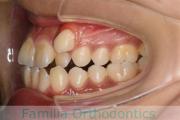

No.21V-298

- 主な症状:

- 上顎前突

- その他の症状:

- 叢生

- 年齢:

- 25歳

- 性別:

- 女性

- 抜歯部位

- 上:

- 44

- 下:

- 55

- 主な使用装置:

- FEA

- 治療にかかった費用:

- 90万円

でこぼこと口元が出ている横顔が気になるとのことで来院されました。重度の叢生(ガタガタ)と側方へのズレがあるため、アンカースクリューを併用したマルチブラケット法にて治療を行いました。3年弱、35回程度の通院をしていただきました。叢生が強いため、部分的にガタガタが再発・後戻りするリスクが高いケースでした。